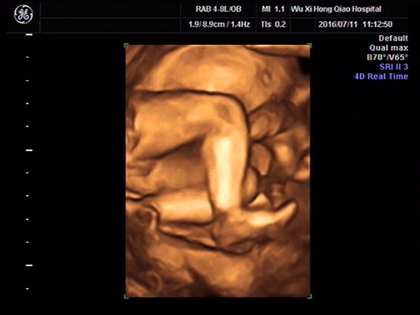

网上有一种说法是,在做四维彩超的时候,如果是女宝宝是比较不容易配合的,如果是男宝宝更容易通过,那么是不是四维女宝更容易配合呢,四维女宝特征有哪些?

很多网上的说法是女宝宝在做B超检查的时候更不容易配合,其实这种说法是没有依据的,宝宝在妈妈肚子里的时候会胎动,也会自己变换姿势,这是正常的,宝宝不配合和性别是没有关系的,如果做四维的时候想要让宝宝配合,那么就要想办法咯。